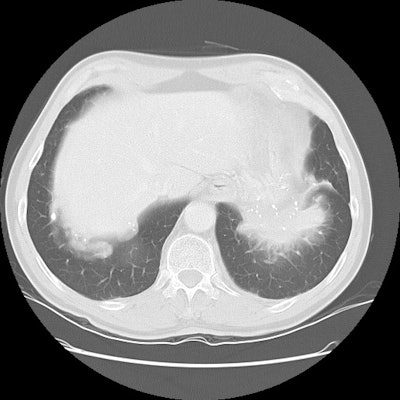

The patient shown on the CT images below presented for evaluation of an enlarging abnormality on CXR. The CT demonstrates exuberant pleural plaque disease along the right diaphragmatic surface. There is a soft tissue mass within the left lower lung that contains a large eccentric calcification. Lung markings radiate into this lesion from the adjacent lung parenchyma and there is distortion of the major fissure. The finding suggested rounded atelectasis, however, the lesion had more aggressive features more inferiorly (see lower CT images). PET images are shown below CT's.